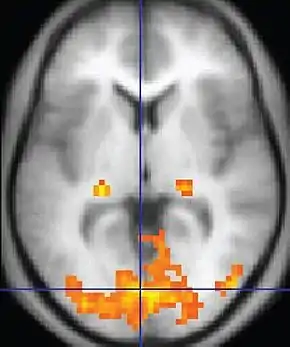

| Functional MRI (fMRI) | Blood-oxygen-level dependent imaging | BOLD | Changes in oxygen saturation-dependent magnetism of hemoglobin reflects tissue activity.[78] | Localizing brain activity from performing an assigned task (e.g. talking, moving fingers) before surgery, also used in research of cognition.[79] | ![]() |